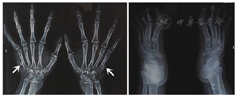

实验室检查:血、尿常规,肝、肾功能和血糖均在正常范围内。染色体检查结果,正常核型,46XY。双手双足X线(正侧位),双手第五掌骨近端尺侧骨性突起;双足跗跖关节面骨质形态欠自然,足趾走行欠佳(图5)。遗传学检测,患者携带3种杂合突变:(1)BBS10 c.602G>A;p.C201Y;(2)BBS10 c.539G>A;p.G180E;(3)USH2A c.4397-1G>A。家族史,其父携带杂合突变1(图6)。诊断:双眼Bardet-Biedl综合征。